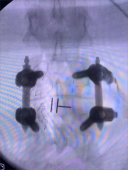

8. 机器人导航辅助下脊柱侧弯矫正技术

脊柱侧弯是一种复杂的脊柱三维畸形,其中以青少年特发性脊柱侧凸最常见。皇冠娱乐城

在浦口地区率先开展机器人导航辅助下脊柱侧弯矫正术,实现了脊柱侧弯手术准确、微创、智能化的突破,获得了良好的效果。还有老年人退变性侧弯,机器人亦可精准置入困难椎弓根螺钉,误差只有0.3mm。